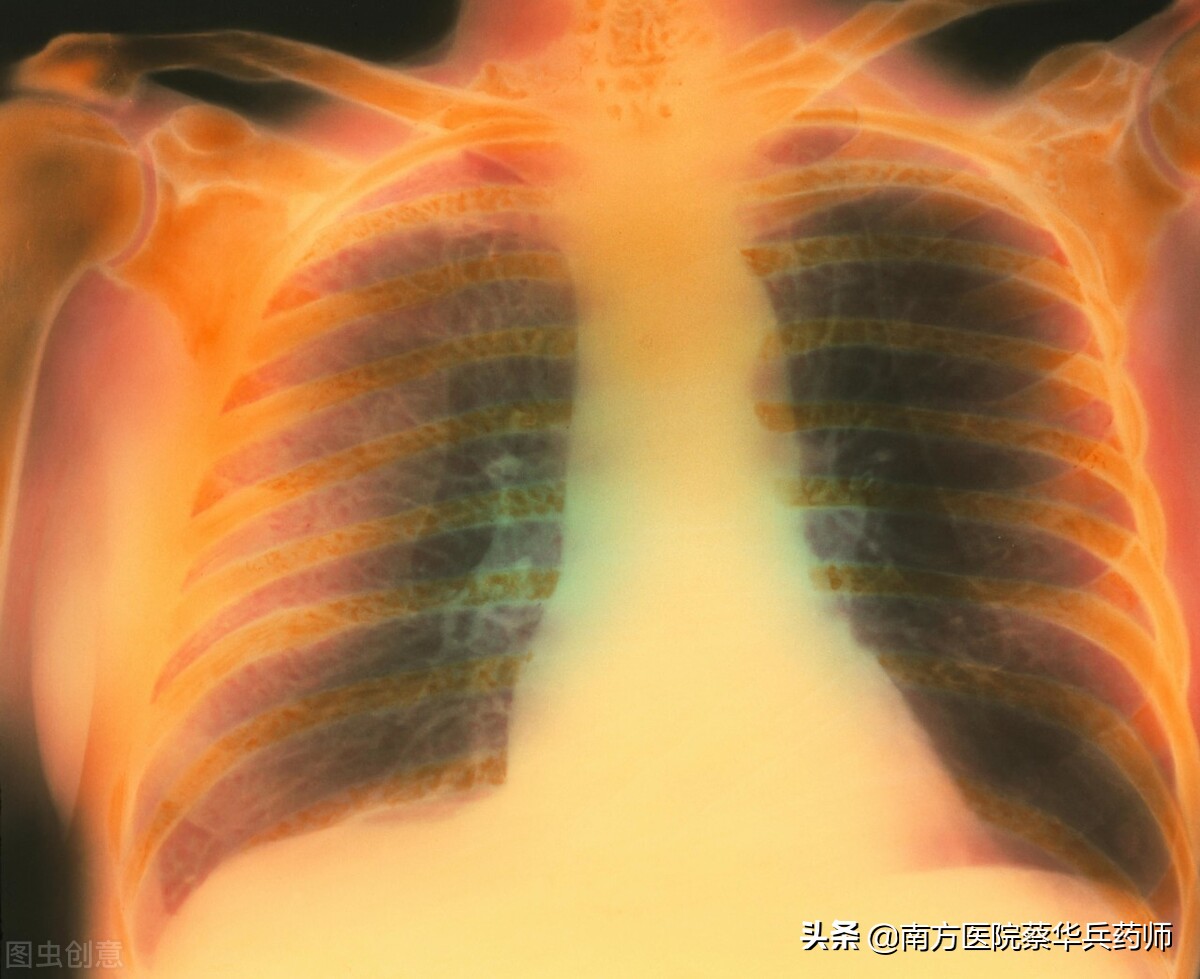

老许是一名67岁的肺气肿患者,他已经被这讨厌的疾病折磨十二年了,并且现在越来越严重。每到冬天,他就像走了一趟“鬼门关”。

慢性支气管炎、肺气肿属寒饮而咳痰清稀者可用本方。